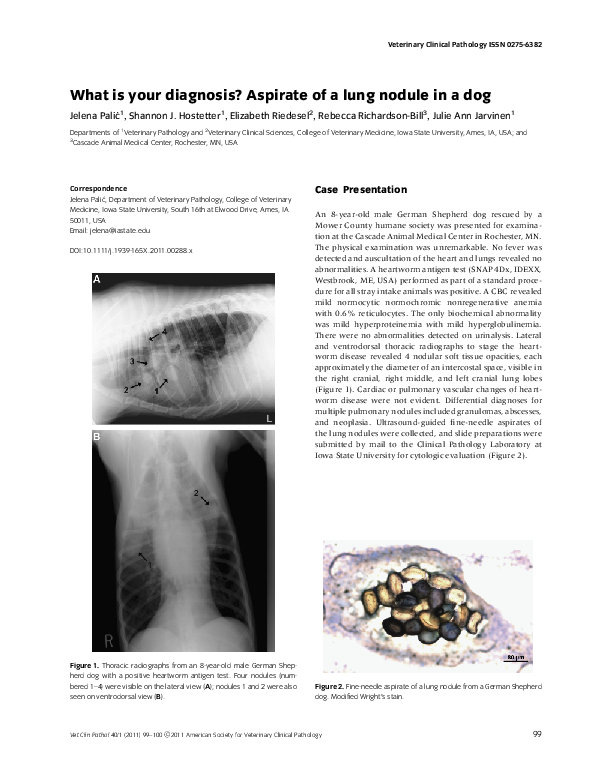

(PDF) What is your diagnosis ? Aspirate of a lung nodule in a dog What Happens If You Aspirate A Pill Into Your Lungs pill aspiration represents a unique type of foreign body aspiration requiring a distinct diagnostic and therapeutic approach. Can a foreign body be aspirated into the lungs? when you aspirate, food, drink, or small objects you've inhaled go into the airway or lungs instead of your stomach. You can also aspirate food that. when a pill enters the. What Happens If You Aspirate A Pill Into Your Lungs.